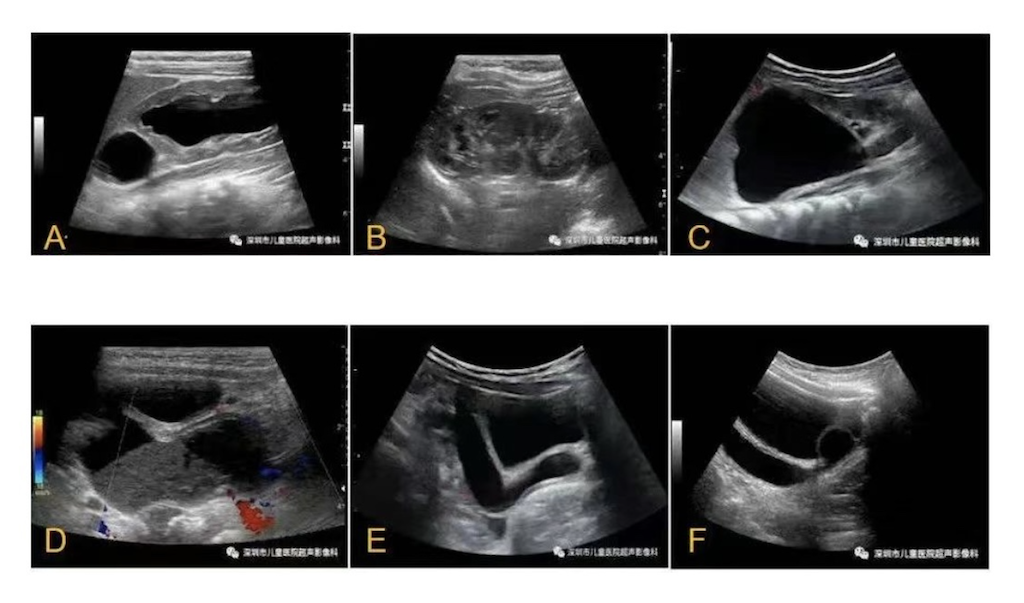

重肾双输尿管畸形是胚胎期输尿管芽发育异常的先天性畸形,指患者肾脏存在上、下两套集合系统,其临床表现各异,完全型重肾双输尿管畸形常伴有上肾部的输尿管囊肿、输尿管异位开口以及下肾部的膀胱输尿管反流;而60%不完全型重肾双输尿管畸形患儿可无症状。重肾双输尿管畸形治疗遵循“简单即最好”。本文旨在科普重肾双输尿管畸形的临床表现及超声结果判读,简略介绍该病的诊疗流程。